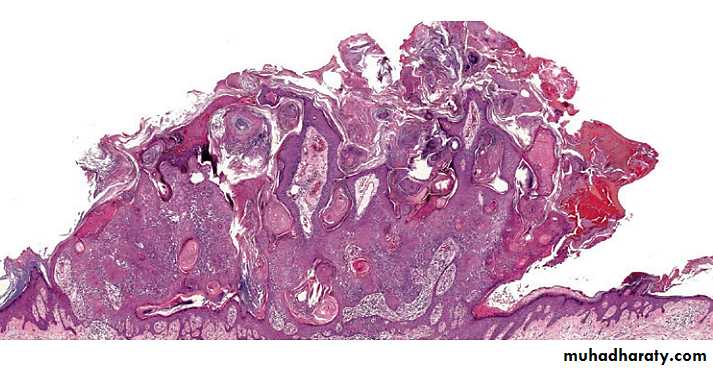

HP of SKs

There are at least six histologic types of SK but different histologic features are often present in the same lesion:

• Acanthotic: the most common.

• Hyperkeratotic: more prominent hyperkeratosis and papillomatosis.

• Reticulated: delicate strands of epithelium that extend from the epidermis in an interlacing pattern.

• Irritated: perivascular, diffuse or lichenoid lymphoid infiltrate. Squamous eddies are common findings.

• Clonal: well­ defined nests of loosely packed uniform cells in the epithelium.

• Melanoacanthoma: shows dendritic melanocytes packed with melanin which is absent in keratinocytes.

HP of SKs  The acanthotic type

Usually presents as a smooth­ surfaced, dome ­shaped papule. Slight hyperkera­tosis and papillomatosis are often present, while the greatly thickened epidermis typically contains a preponderance of basaloid cells.

Sharply demarcated horizontal base called “string”.

Papillae may be narrow in some lesions.

Invaginated horn pseudocysts are most prevalent in this variant.

This type often contains an amount of pigment superior in quantity than others; it is primarily concentrated in keratinocytes and is transferred from neighboring melanocytes and deeply pigmented lesions contain abundant melanin in basaloid cells.

Acanthotic type

with church spires of papillomatosis and hyperkeratosis & preponderance of squamous cells relative to basaloid cells

Hyperkeratotic type

with delicate, lace-like strands of interconnecting epithelium composed of a double row or more of hyperpigmented basaloid cells and interspersed horn pseudocysts

Reticulated type

exophytic lesion with papillomatosis, hyperkeratosis, hemorrhagic crust and dermal inflammation

Irritated type

with Borst–Jadassohn phenomenon* characterized by well-demarcated nests of keratinocytes within the epidermis

Clonal type

* ‘clones’ of basaloid, squamatized, or pale keratinocytes in epidermis appear different than their neighbors